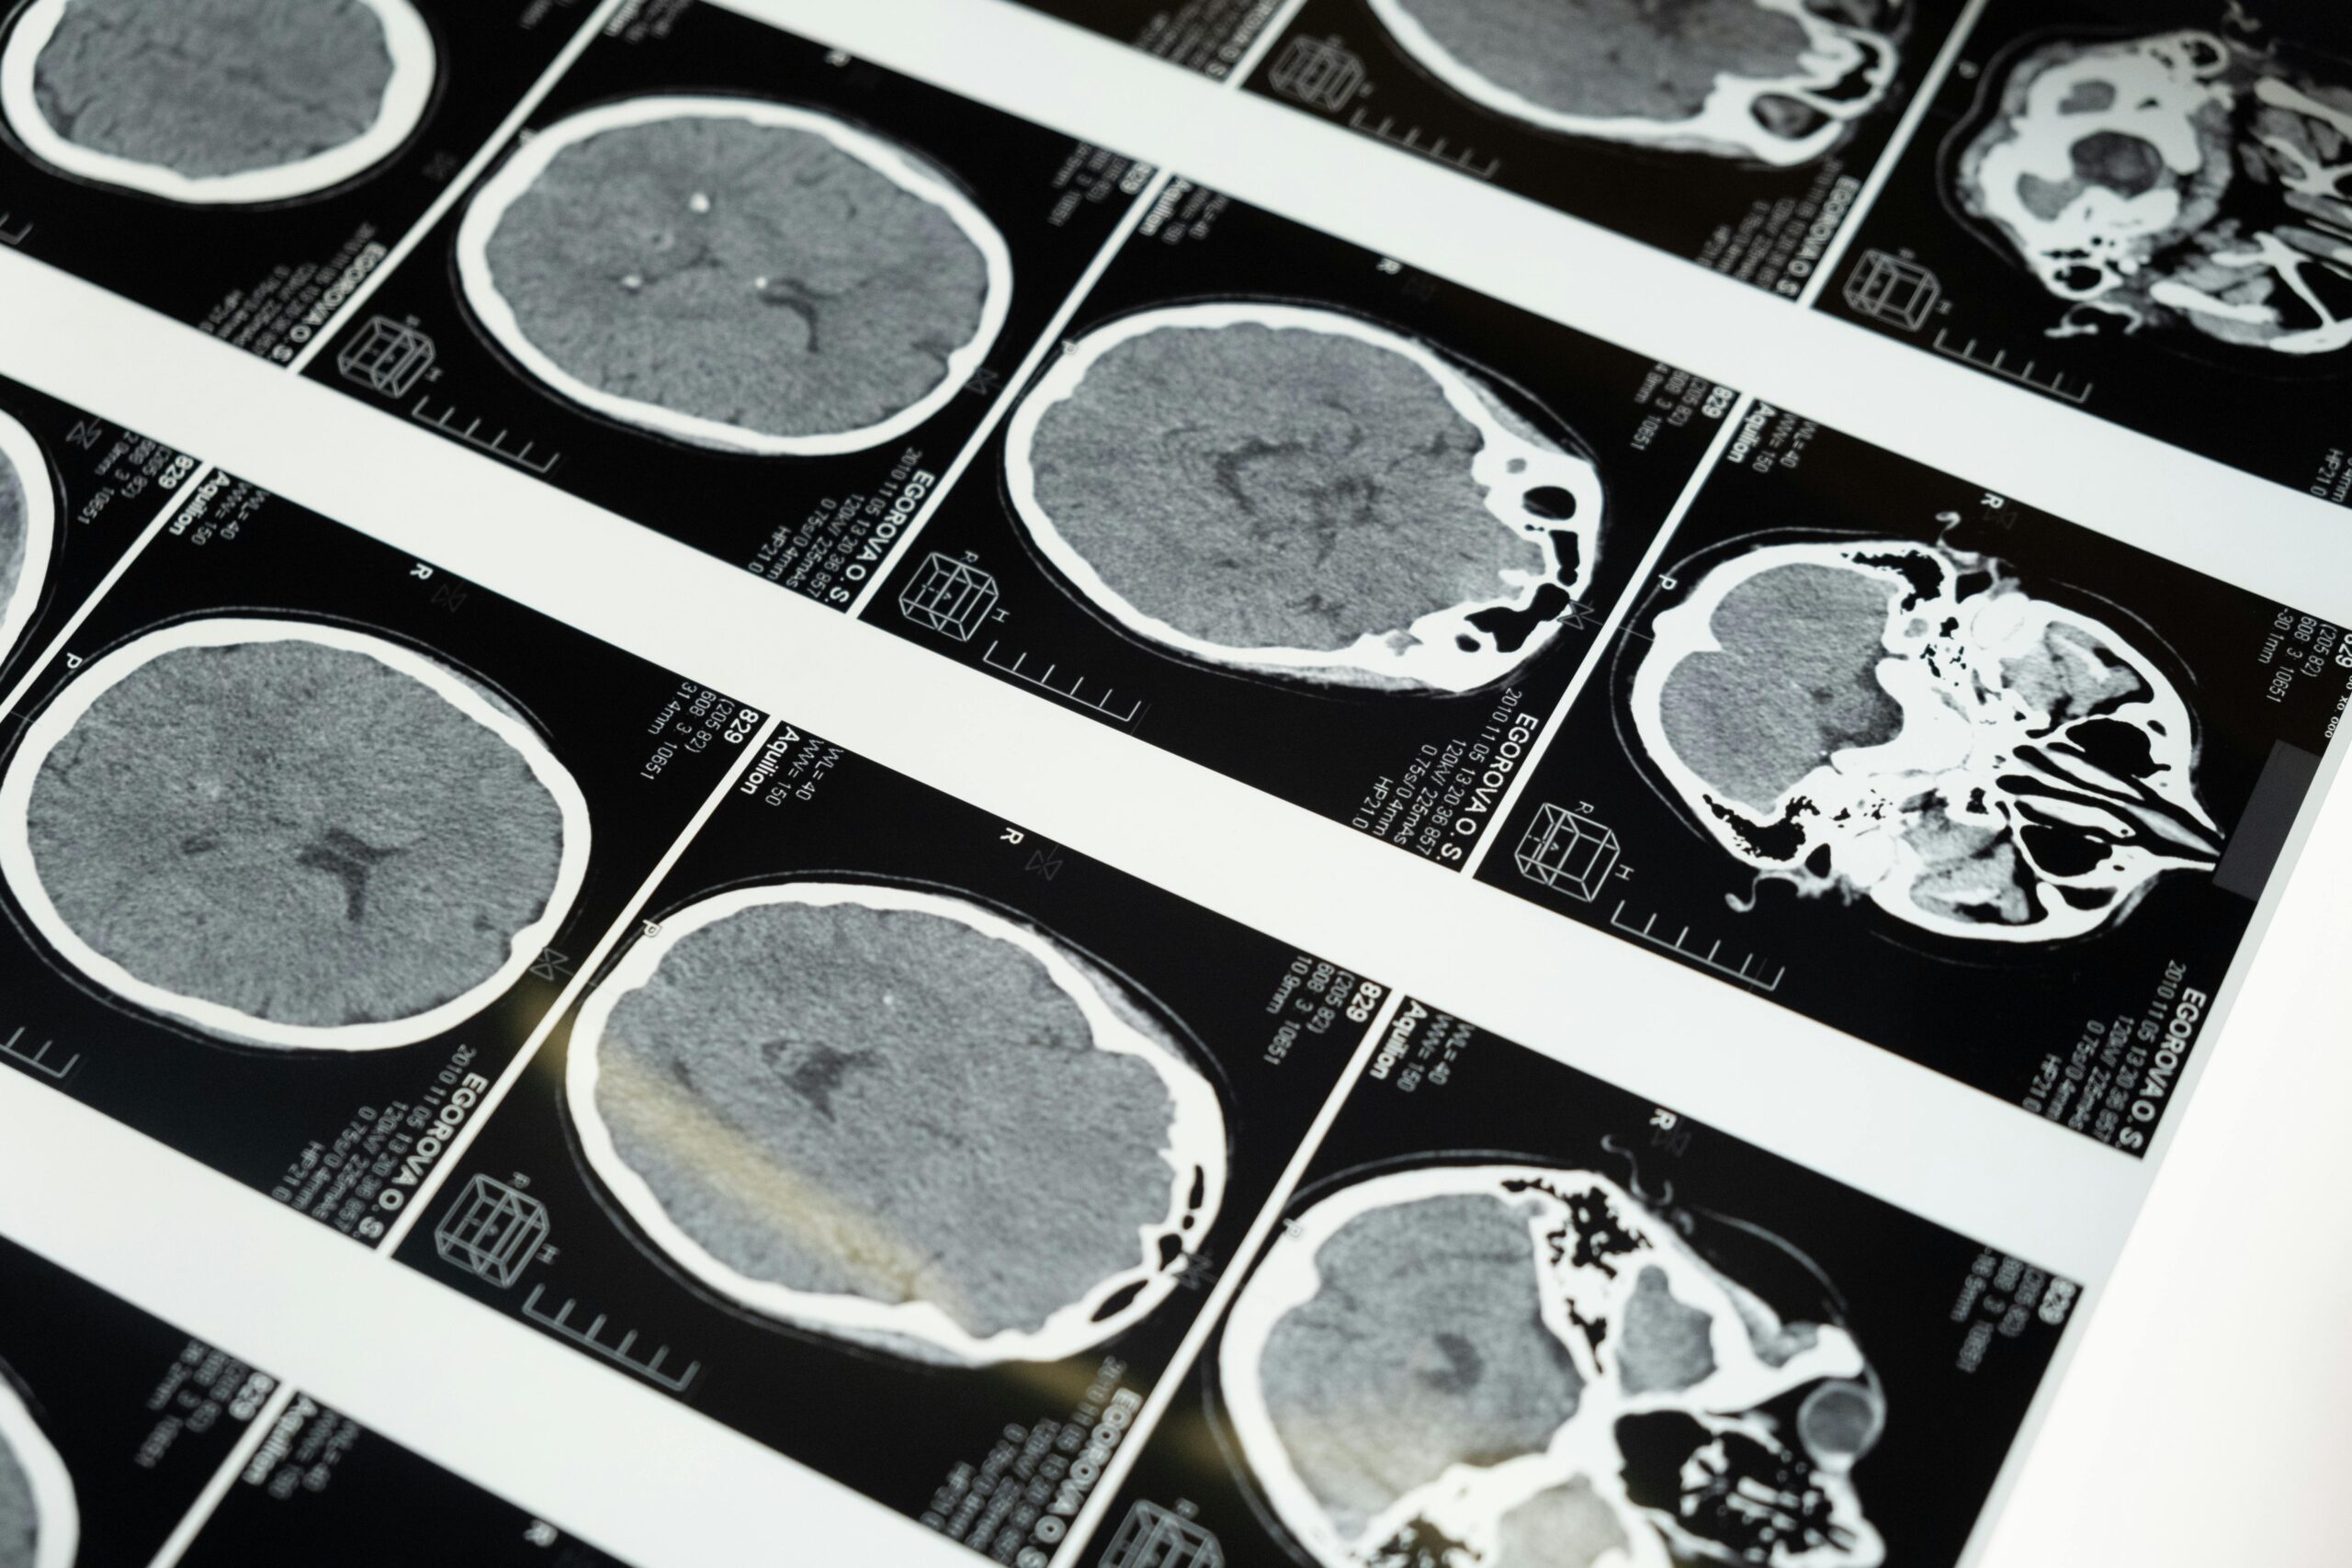

Essas doenças afetam o cérebro. A mais conhecida nos humanos é a doença de Creutzfeldt-Jakob (DCJ). Ela causa perda de memória, alterações de comportamento e de movimentos. A progressão é acelerada e leva ao óbito.

Doenças priônicas afetam o cérebro. São raras, mas perigosas.

O que acontece no cérebro

Vamos simplificar o mecanismo. Todos nós temos a proteína priônica normal (PrPC). Em condições que ainda estamos desvendando, parte dela muda de forma e vira PrPSc, a forma “errada”. Essa forma atua como molde. Encosta na proteína normal e a faz copiar o mesmo erro. É um efeito dominó molecular.

Com o tempo, esses “blocos” mal dobrados se juntam e formam agregados. Eles são rígidos, parecidos com fibras. No tecido, vemos lesões microscópicas que lembram uma esponja. O resultado é perda de neurônios e de funções cerebrais.

Por muito tempo, o diagnóstico definitivo era neuropatológico, ou seja, após o falecimento do paciente analisava-se tecido cerebral. Mas precisávamos de ferramentas confiáveis em vida. Durante anos, nos guiamos por sinais clínicos, ressonância, eletroencefalograma e marcadores como a proteína 14-3-3 no líquor. Eles ajudavam, mas não eram específicas o suficiente.